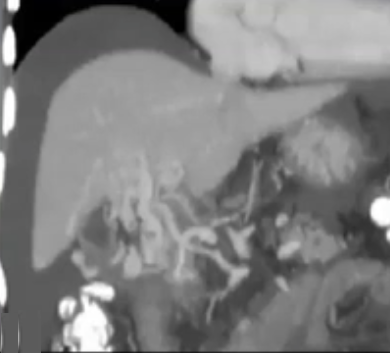

慢性门静脉血栓形成和经颈静脉肝内门体分流术

这些患者大多表现出门静脉高压的症状,而非缺血症状。通常还会伴有出血现象,这使得溶栓药物的使用变得困难。

此外,患者肝脏通常较小且为肝硬化状态,可能还存在海绵状转化,因此经皮穿刺并非可行的选择。

在这种情况下,“Salem ”技术是最佳选择,即进行脾脏穿刺,疏通血栓,放置圈套器,并引导经颈静脉肝内门体分流术(TIPS)操作。

异常肝脏中的 PVT

大多数原发性肝性脑病病例发生在肝硬化患者身上,并且通常为慢性病症。

在这些情况下,异常肝血窦中的高阻力会在溶栓成功后导致持续的高门静脉压力,从而可能引发再次血栓形成。

这些患者将从减压型经颈静脉肝内门体分流术(TIPS)中获益。

此外,TIPS 术后血流速度(SMV/SV)的增加有助于维持静脉的通畅性。

经颈静脉肝内门体分流术(TIPS)可能会引发这些患者出现肝性脑病(HE),不过这种情况可以通过药物治疗来控制。